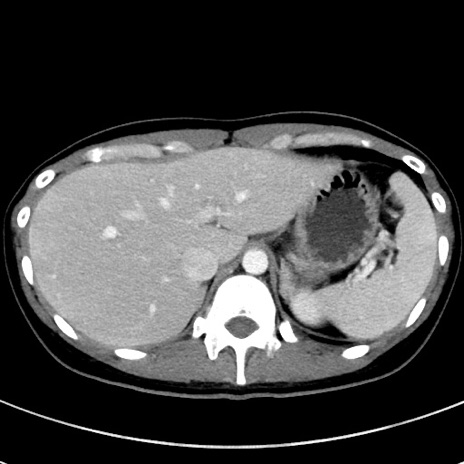

冠状断像

【症例】20歳代女性

【主訴】嘔吐、下腹部痛

【現病歴】昨日夕食後に嘔吐し下腹部痛が出現。本日になっても嘔吐持続し改善しないため来院。

【身体所見】意識清明、BT 37.2℃、BP 108/67mmHg、腹部:平坦、やや硬、下腹部正中から右にかけて圧痛あり、反跳痛軽度あり、tapping pain(+)。

【データ】WBC 13600、CRP 14.94